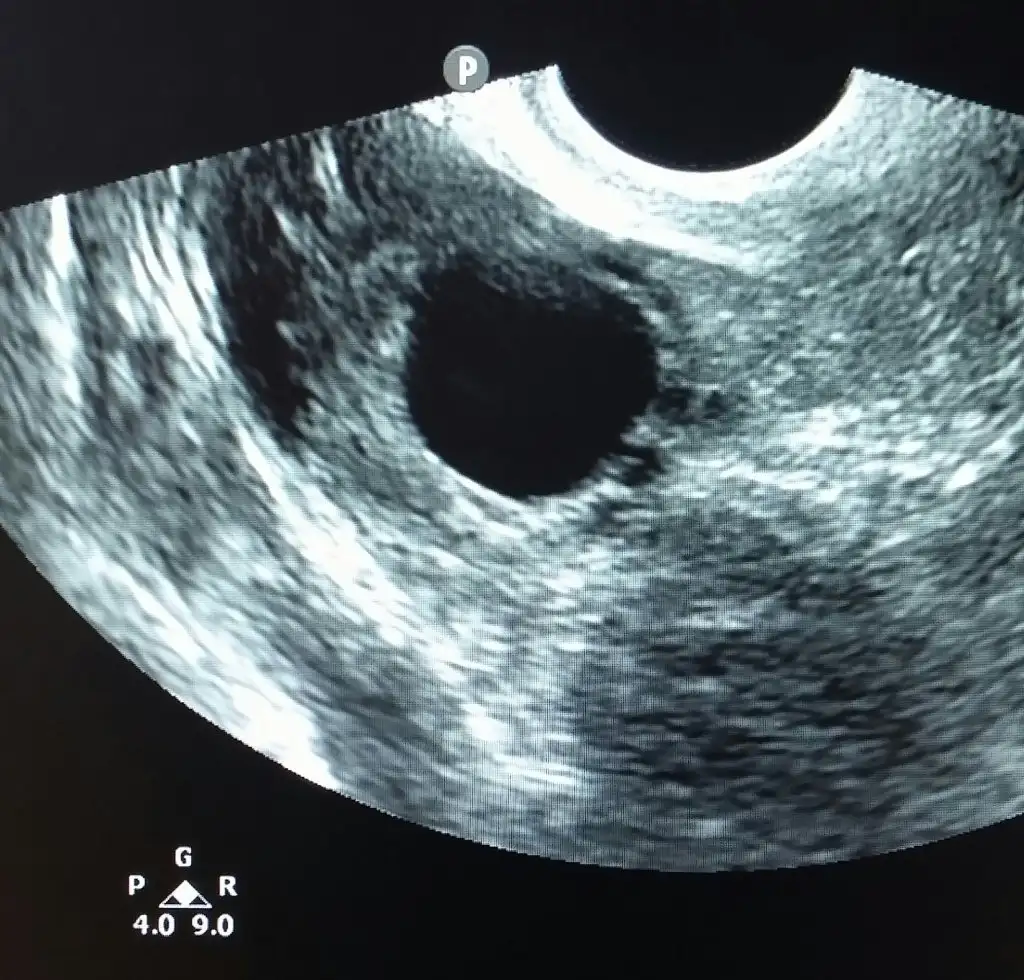

SAĞ TARAFTAKİLERDEN MEMNUNDU CANIM İŞTE 18-21 MM6 yumurtan vardı canım pekı dr yumjrtalara ne dedı yanı ıyı guzel dedımı sen gordun mu yumları bole yuvarlak oluyo ve hatları cok belırgın oluyo yarın telden ıkı resım goıstercem sana bırı kalıtesız yumurtam olmustu o dıgerı de bebegımın yumurtası

BUNA DAHA ÇOK BENZİYORDU CANIM BÖYLE GÖRDÜM AMA YİNE DE BİLEMİYORUM Kİ NE DESEM ALLAH BİLİREki Görüntüle 1574106 Bu da kaliteli yumurta seninkiler hangisine benziodu

o zaman yumuslar kalıtelı kalıtelı gelmişlerrrrBUNA DAHA ÇOK BENZİYORDU CANIM BÖYLE GÖRDÜM AMA YİNE DE BİLEMİYORUM Kİ NE DESEM ALLAH BİLİR